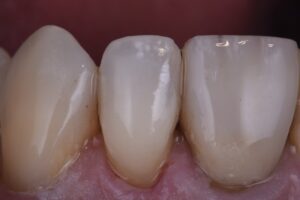

April 18, 2021 Incipient caries removal with this invisible restorative, #GC #EssentiaU Previous Post Next Post